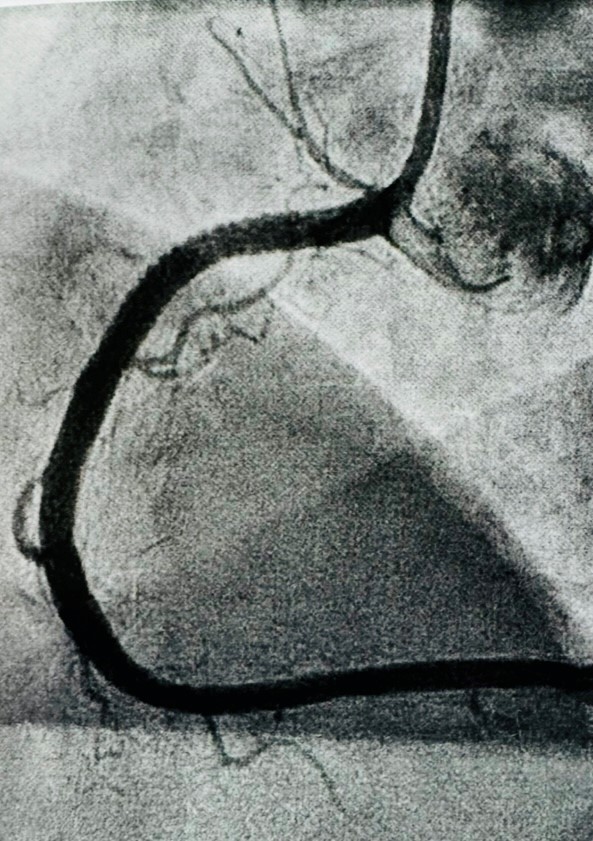

An angiogram revealed multiple blockages – 100% obstruction of the right artery, and 70% of the left. It’s a miracle that I’m still alive and kicking. I could have suffered a heart attack and dropped dead whilst swimming or hiking.

I was once blind (to the conditions of my heart), and now I see. Lying on the table in the operating theatre, I could literally see the dye illuminating the blocked arteries. They looked like twisted ropes or branches on a tree, with some portions narrower than they should be.

The plan was to fix the fully obstructed right artery first, and then the left in the following week. The first angioplasty went smoothly. After an overnight observation, I was discharged the following day with two stents amounting to a total length of 66 mm and wounds in my groin and wrist.

Before first angioplasty After first angioplasty

Feeling relieved to have escaped the need for a heart bypass, I remained cautious not to celebrate too soon. The treatment is only halfway through. Thankfully, the second angioplasty went extremely well too. And as the catheter was inserted through the wrist instead of the groin, recovery was much easier. I could walk and was discharged the same day.